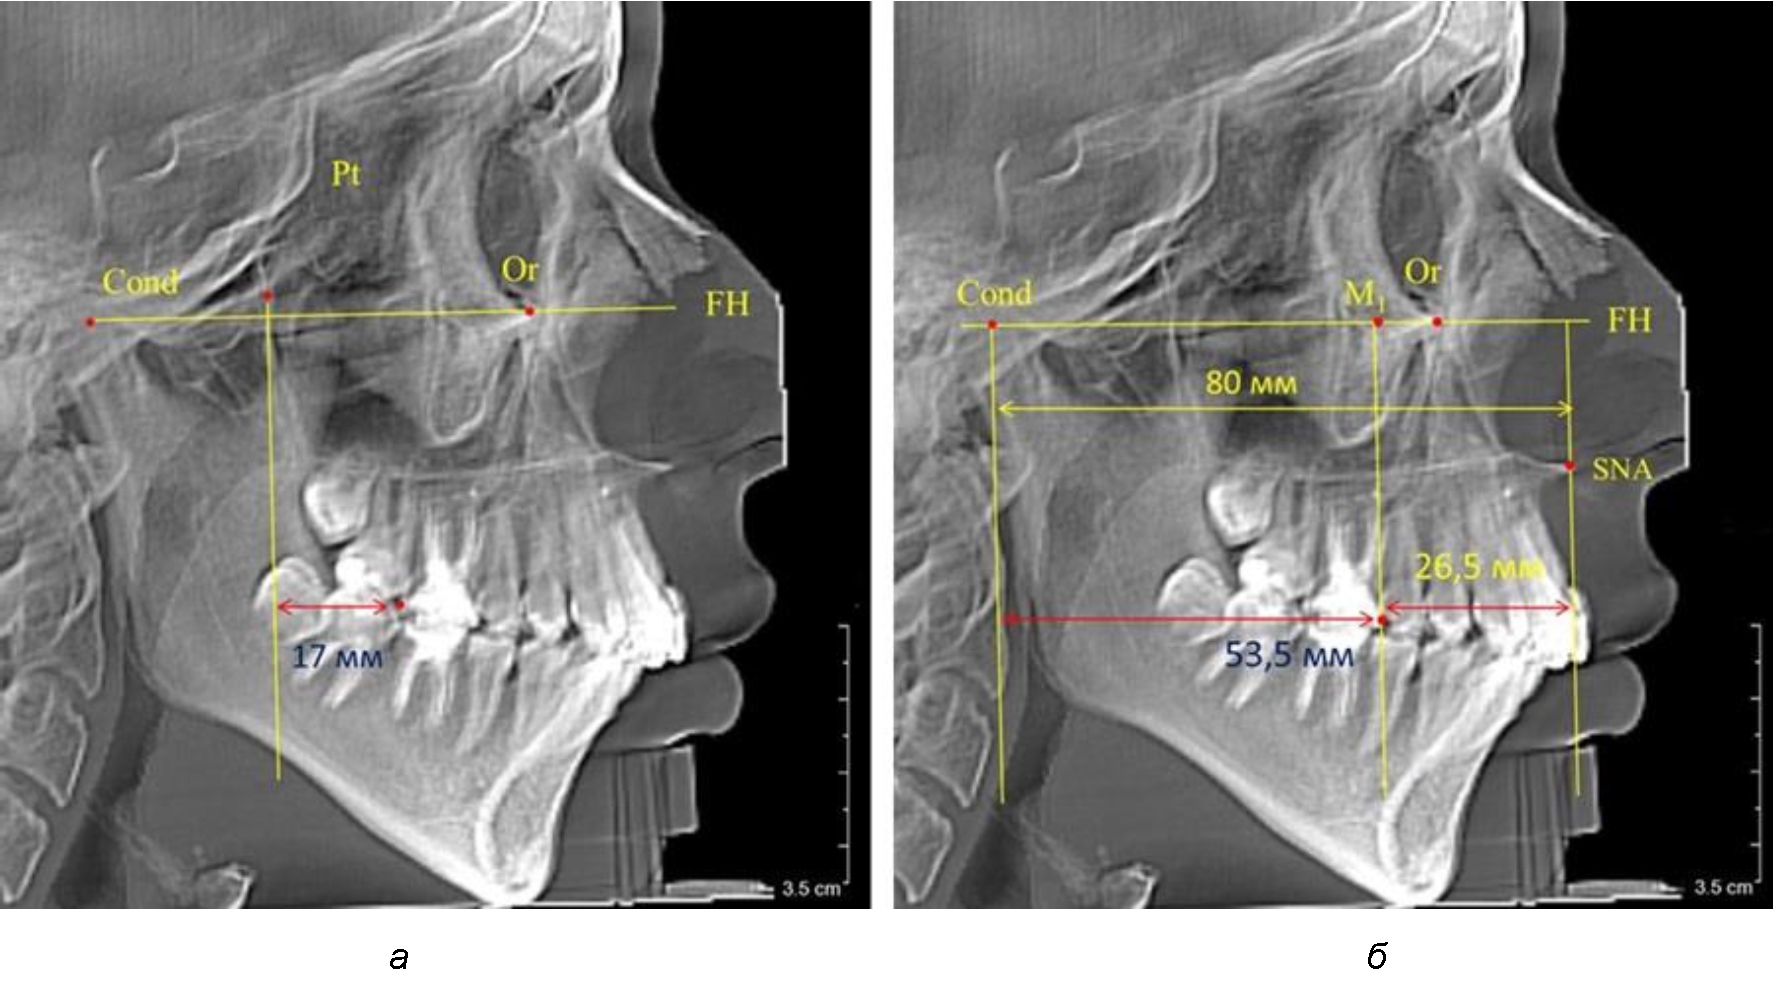

Таким образом, для прогнозирования оптимального положения первых постоянных моляров наиболее целесообразным методом явилось использование относительного показателя, что подтверждено при анализе рентгенограмм с минимальными и максимальными значениями по методу R. E. McDonald.

Так, при расстоянии от крыловидной вертикальной плоскости PTV до дистальной поверхности верхнего первого постоянного моляра в 13 мм сагиттальный размер гнатического отдела был 82 мм. При этом отношение кондилярно-спинального расстояния к кондилярно-молярному размеру (54,5) было близким к коэффициенту 1,5, что представлено на рис. 2.

Рис. 2. Особенности положения первых моляров по R. E. McDonald (а) и по предложенному методу (б) при уменьшенном молярно-крыловидном расстоянии